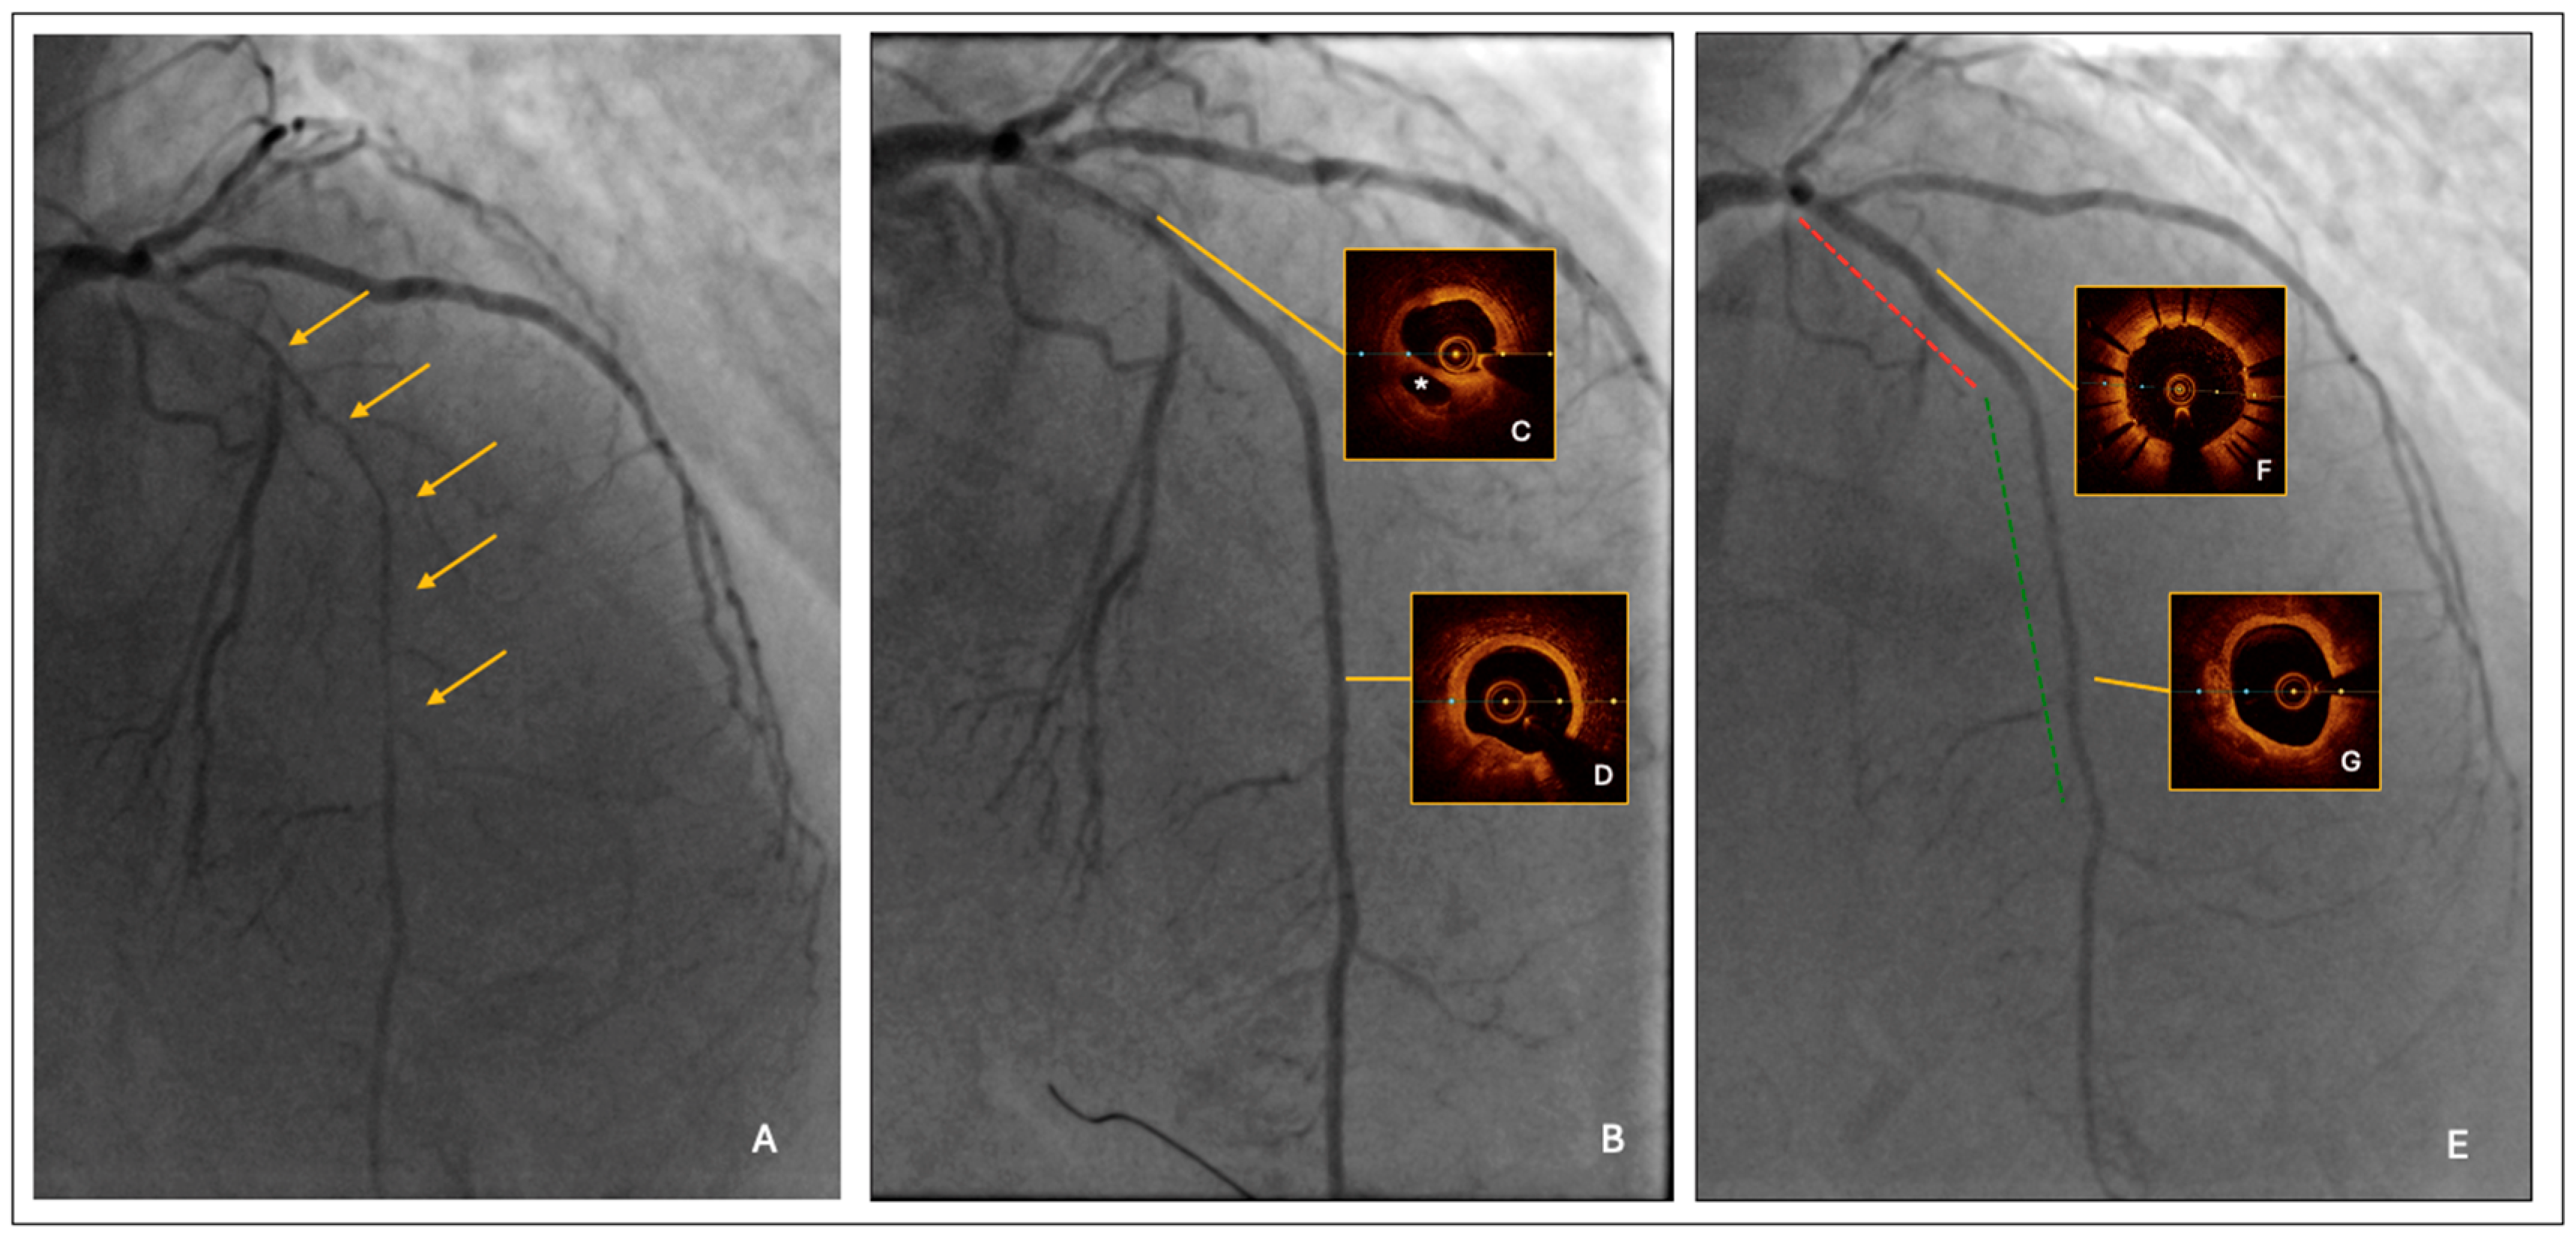

- Lesion predilatation by a semi-compliant balloon, sized 1:1 to the reference vessel diameter; it was 2.0 mm at the distal segment and increased progressively up to 3.0 mm at the proximal segment, respectively. After lesion predilatation, the result was optimal in the middle-distal LAD, but suboptimal in the proximal segment, where a long linear dissection was observed (Figure 1B).

- Intravascular imaging by optical coherence tomography (OCT) confirmed an adequate overall luminal gain and confirmed the presence of a large linear dissection in the proximal LAD, with significant residual stenosis and a moderate burden of calcium (Figure 1C,D).